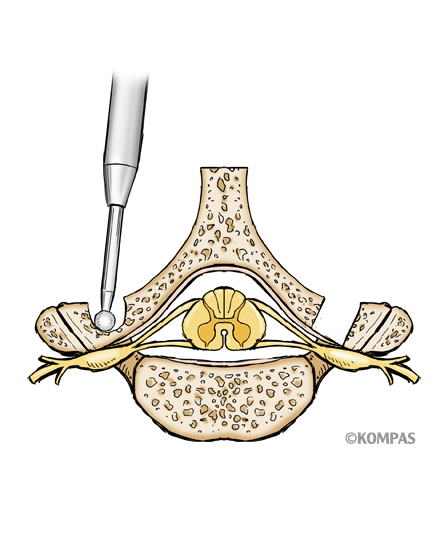

頚椎椎弓形成術(片開き式脊柱管拡大術)

適応となる疾患:頚椎症性脊髄症、頚椎後縦靭帯骨化症など

1978年に慶應義塾大学医学部整形外科平林名誉教授が考案した片開き式脊柱管拡大術(ELAP) は、海外でも頚椎の後方除圧術式として標準的な手術です。術後の長期成績も安定しておりまた高齢者にも安全に行える手術です。当院では従来法をさらに改良し、開大した椎弓の再閉鎖を防止するために椎弓プレートを使用して、手術後の頚部痛軽減、神経麻痺予防に努めています。また頚椎の不安定性(すべりやぐらつき)や変形(弯曲異常)のある患者さまには、金属による固定術を併用することで術後成績の向上に努めております。手術時間は1時間から1時間30分ほどで、翌日から歩行が許可されます。入院期間は通常10~14日間ぐらいになります。